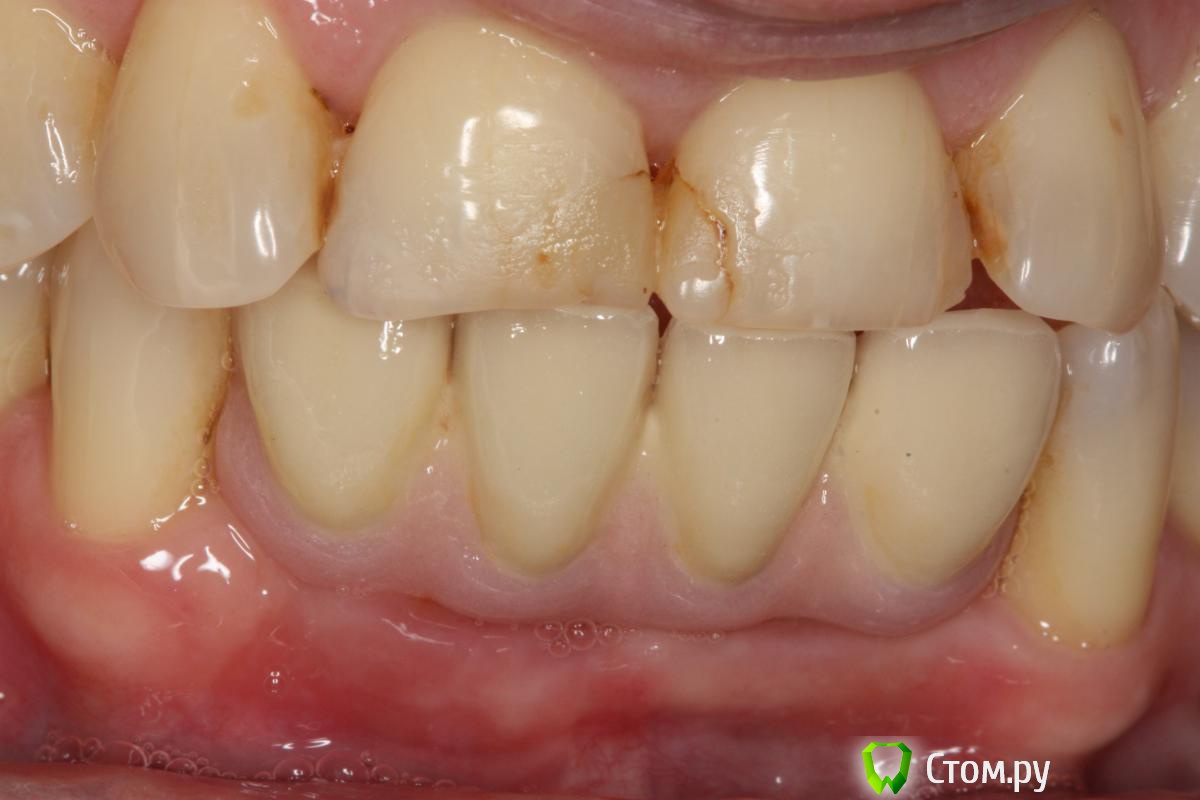

Pavel-Pskov Опубликовано 18 апреля, 2014 Автор Поделиться Опубликовано 18 апреля, 2014 Присоединяюсь к вопросу. Интересна первичная ситуация: какова ширина была?5-6 мм. Одномоментно с удалением. 41 и 31 были вообще не в кости 42 и 32 где то на 2-3 мм. Ссылка на комментарий

Pavel-Pskov Опубликовано 6 ноября, 2014 Автор Поделиться Опубликовано 6 ноября, 2014 подскажите, почему при такой толщине не поставить 3.75?НА медиальных 2-3 витка вестибулярно были не в кости , пришлось подсыпаться под ламину. Ссылка на комментарий